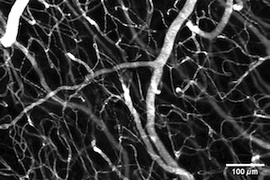

Boston University spots stalled blood flow in brain capillaries

Two-photon Bessel beam approach allows fast volumetric imaging to spot circulation problems.